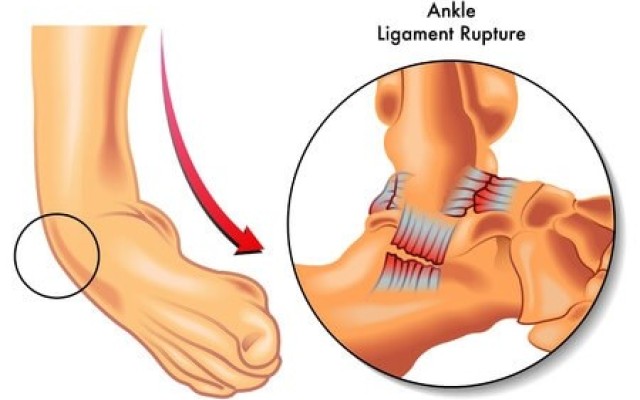

Posted in Dr Kaushik Hazratwala Blogs on Monday, 11 September 2017 by Kaushik Hazratwala

Chronic ankle instability is a condition characterized by a recurring giving way of the outer (lateral) side of the ankle. This condition often develops after repeated ankle sprains. Usually, the giving way occurs while walking or running on uneven surfaces or sloped surfaces. Most people who suffer an ankle sprain will recover with Physio and retraining. A select small number go on to develop...5 Steps to Finding the Perfect Life after Knee Replacement

Posted in Dr Kaushik Hazratwala Blogs on Friday, 21 July 2017 by Kaushik Hazratwala

Ankle fractures can occur during sporting activities, or as a result of a fall. Fractures can occur in the tibia, fibula or a combination of both, and damage can also involve the ligaments of the ankle joint. Depending on the type and location of the fracture, surgery may be required. Dr Kaushik Hazratwala - Ankle surgery specialist Depending on the success and stability of the...Orthopaedic Research Institute of Queensland (ORIQL)